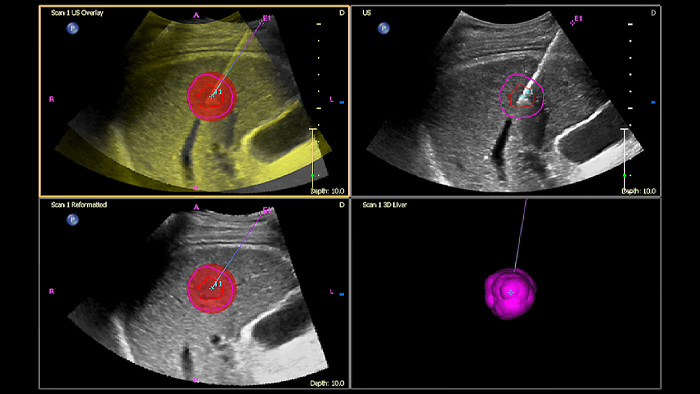

Treffen Sie auch in diagnostisch schwierigen Fällen die richtige Entscheidung mit den Philips Funktionen zur Bildfusion und Nadelnavigation. Ein effizienter Arbeitsablauf ermöglicht Klinikteams eine schnelle und effektive Fusion von CT/MRT/PET mit Live-Ultraschallbildern, wobei die Nadelnavigation die Biopsieführung bei kleinen, schwer zugänglichen Läsionen unterstützt.³

Mit der Tumorkontur können Anwender Läsionen mit einem halbautomatischen Tool planen und hervorheben. Es erleichtert das Zeichnen einer 3D-Kontur um die relevante Struktur und bietet so Unterstützung in schwierigen Fällen, bei denen die Läsion nicht einfach zu erkennen ist.